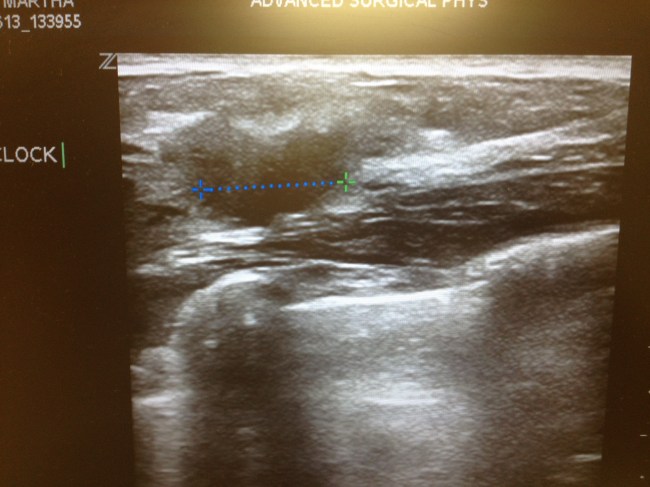

I took a picture of the tumor on the ultrasound screen before I left. I’m not sure why, but I did. Here it is — all 1.8 cm of it.